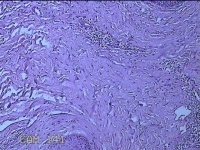

性别

男

年龄

45岁

临床诊断

皮下结节

一般病史

发现左侧一结节,伴局部瘙痒不适1年。

标本名称

左侧结节

大体所见

灰白暗红色带皮肤样结节0.8x0.7x0.3cm一个,表面糜烂,切开结节呈实性,切面灰白粉红色,质软。

感觉像表皮样囊肿?